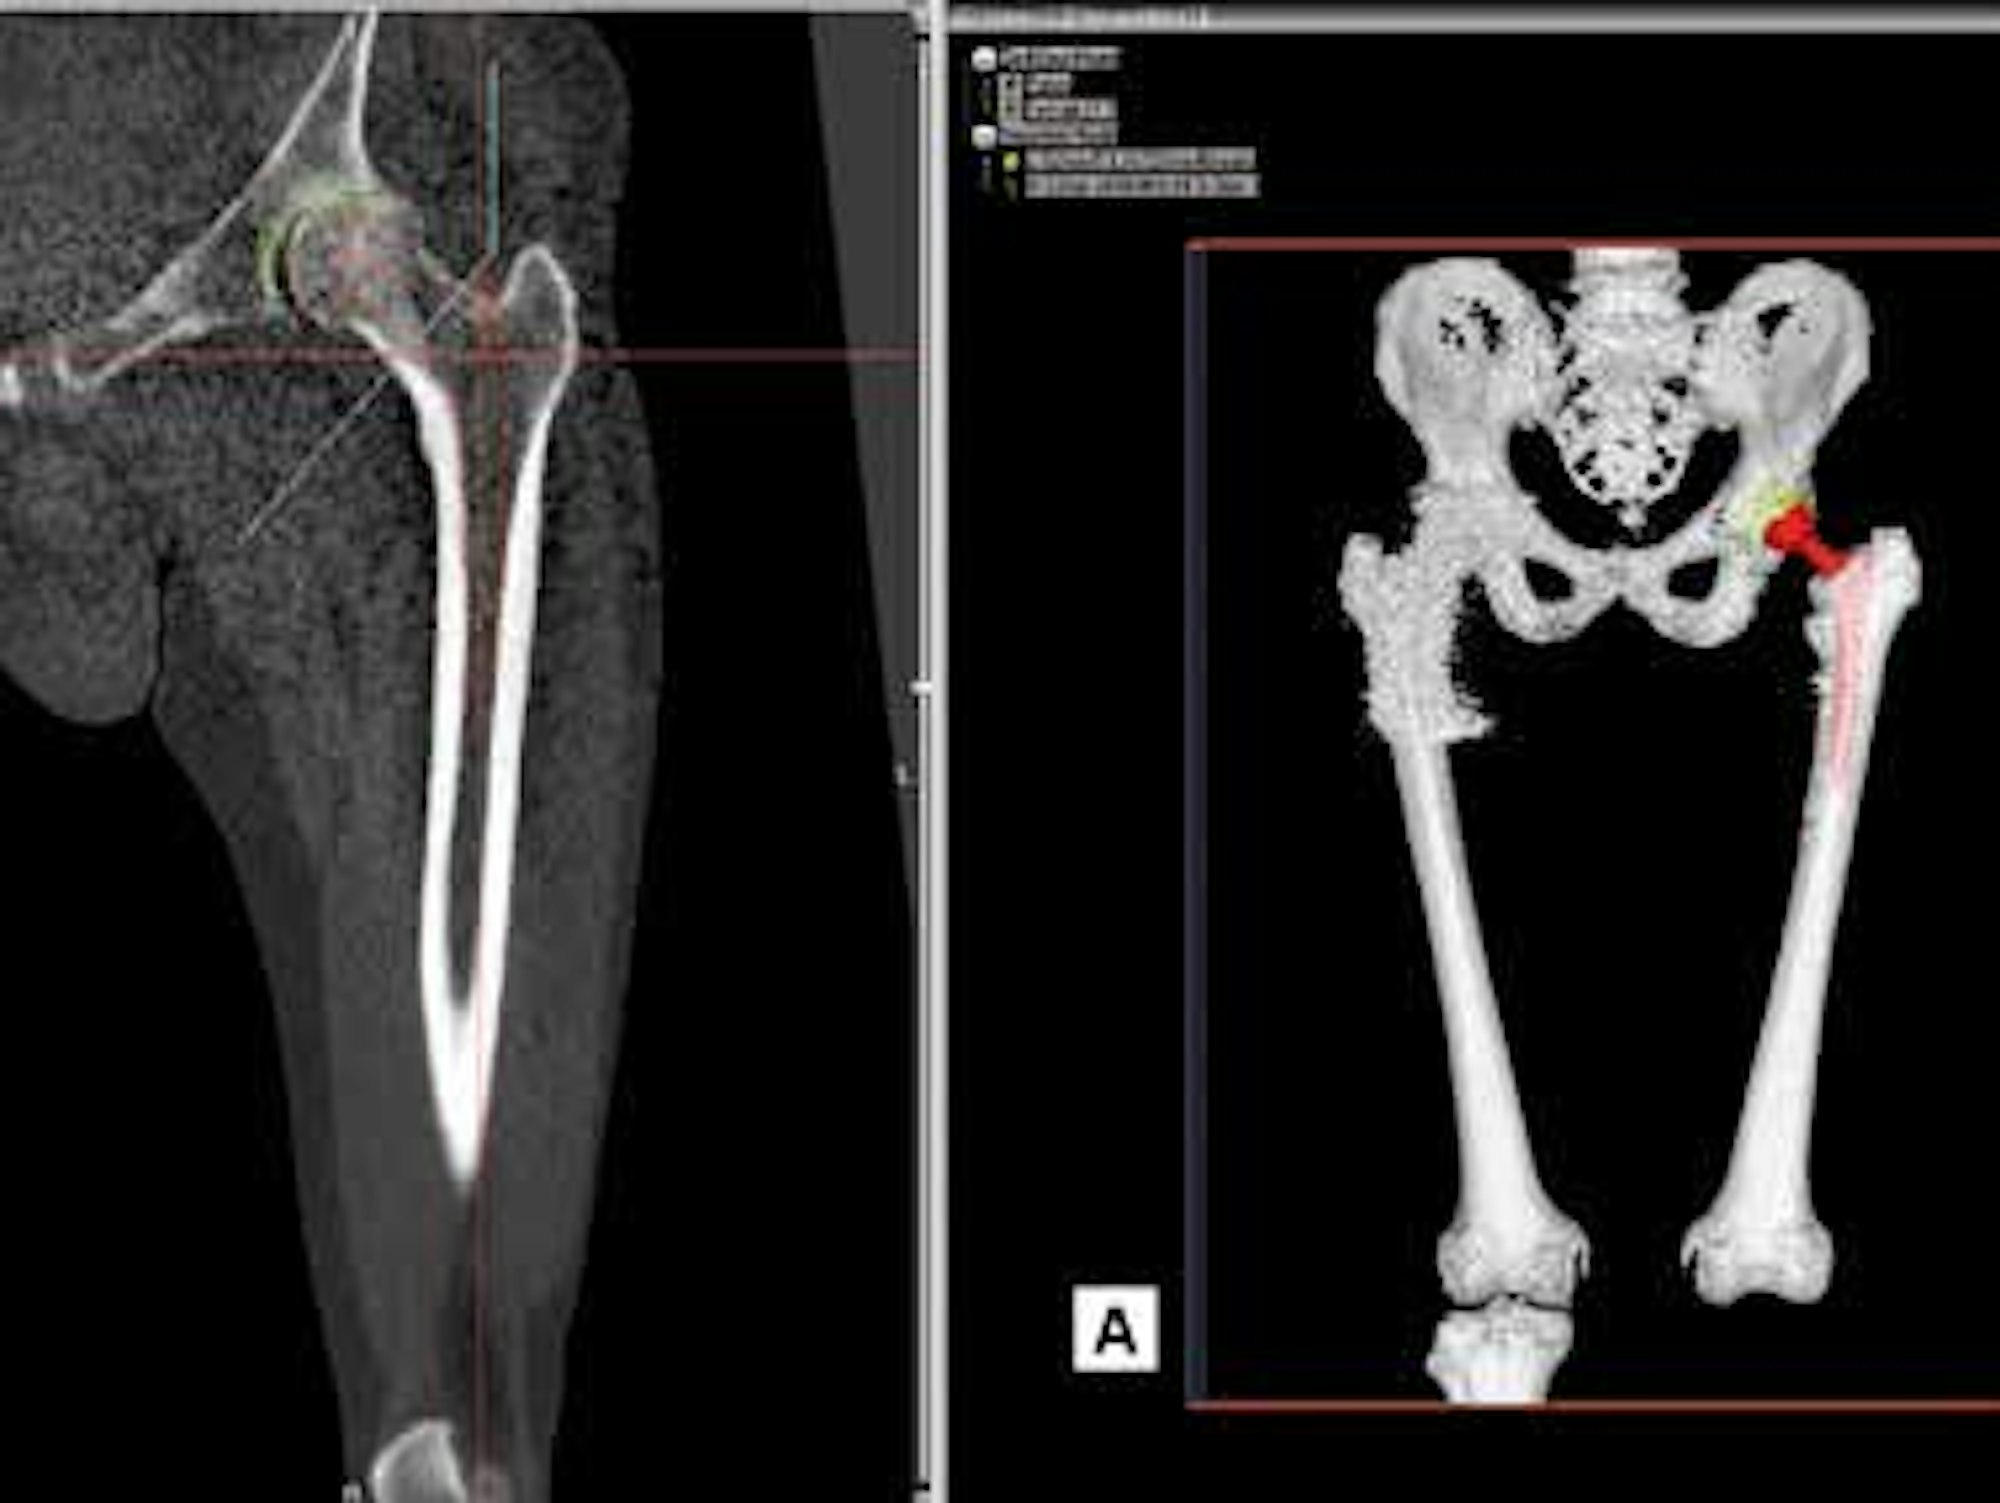

Mit der neuen Konstruktionssoftware wird eine dreidimensionale Planungsebene geschaffen, in welcher das jeweilige Gelenk von drei Ebenen aus betrachtet werden kann. Der behandelnde Orthopäde kann die unterschiedlichen Implantate, Größen und Formen virtuell einsetzen und sieht so, welche Prothese am besten zum Körperbau des Patienten passt. So kann er dem Patient bereits vor der OP sagen, welche Endoprothese er erhalten wird. Auch die neuen Bewegungsabläufe mit dem künstlichen Hüftgelenk können so erstmals virtuell simuliert werden. Ziel des neuen Verfahrens ist es, dem Patienten eine maximale Passgenauigkeit seines Gelenkersatzes zu bieten.

Die neue Methode erlaubt es den Operateuren auch, vor der OP die Frage sicher zu klären, ob eine Versorgung mit einer Standard- oder einer Individualprothese sinnvoll ist. So bietet die vorausgehende Planung und die exakte Prognose eine maximale Sicherheit für den Patienten.